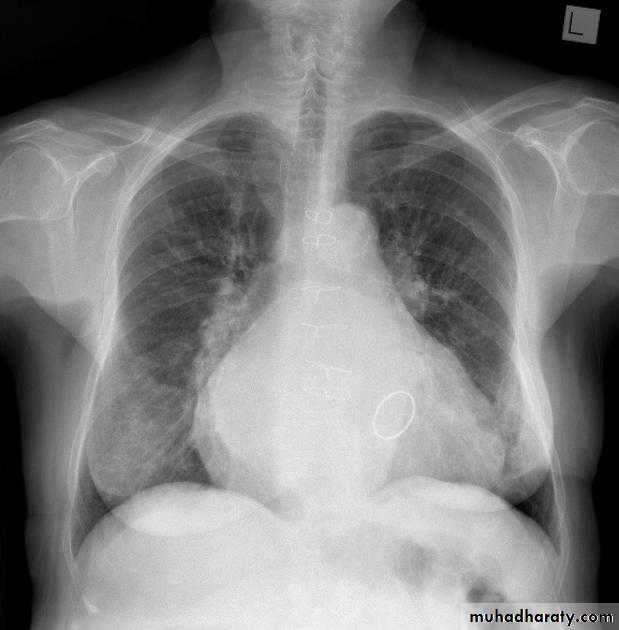

What is the main difference between 2 films ??? What is the shape of each one ??? A. B.

44.A.RT middle lobe consolidation

B.RT middle lobe collapse